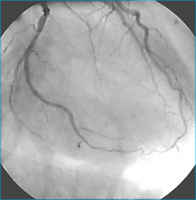

Rekanalisation - Ballondilatation

Abbildung 4: Nach erfolgreicher Rekanalisation und Ballondilatation.